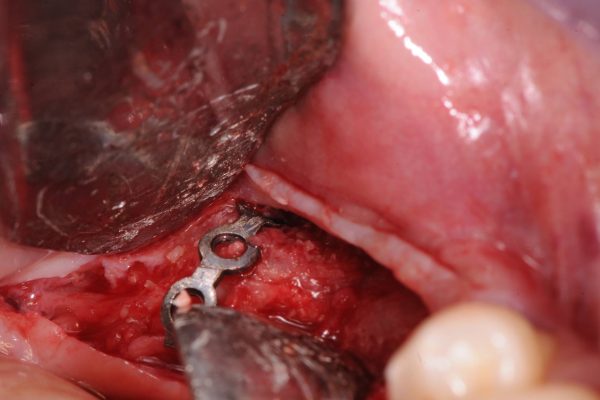

Il caso Clinico:

Importante perdita ossea Verticale ed orizzontale provocata dalla perdita di Impianti posizionati a causa della MANCANZA di una attenta diagnosi, piano di trattamento e capacità operativa, che avrebbero mostrato l’impossibilita di posizionare gli Impianti senza ripristinare lo spessore osseo adeguato …